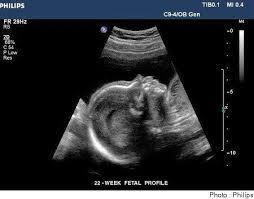

Vue de côté, le bébé regarde vers le haut, en blanc les os. Identifier les anomalies structurelles l'échographie morphologique peut détecter. L'échographie est une technique d'imagerie non irradiante utilisant les ultrasons qui sont émis par une sonde que le médecin radiologue pose sur la peau.

Elle permet de détecter des malformations et de surveiller le développement du fœtus. Alors avec une image 3d, c'est plus facile à. A trois semaines de grossesse, votre corps commence à changer.